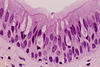

What is this tissue type? What are its characteristics? Where is it located?

Type: Simple columnar epithelium

Description: A single layer of tall cells with round-to-oval nuclei located at the base of the cell and some cells bear cilia

Location: Digestive tract (absorption and secretion; ciliated types propel mucus)